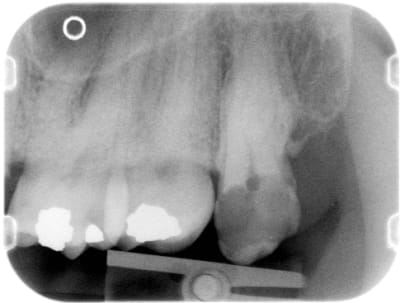

on voit qu'effectivement elle avait de belles hanches...

l'image est trompeuse, on voit le palais osseux en perspective mais le trait vertical d'alvéolectomie juste en distal de 27 reflète la réalité clinique.

belle regularisation de crete osseuse, que tu ne peux même pas coter car faite au cours de la séance d'extraction.

Par contre, moi je vois sur tes radios, des amalgames, qui mériteraient eux aussi des avulsions, mais beaucoup plus conservatrices ;)

Vu les clichés elle semble accessible alors pourquoi pas: endo-ic-co avec une éventuelle élongation coron. ?

la 27 paraît comme un arbre suspendu en haut des falaises d'Etretat.